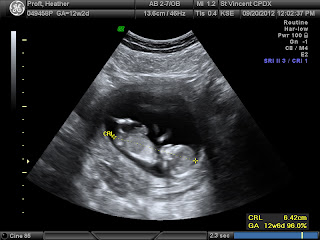

We did make it to 12 Weeks so the chances of a miscarriage have dropped to 1%. Then we hit 13 Weeks and had the pre diagnostic testing done for Down Syndrome and a few other chromosomal disorders. They all came back negative and also told us the sex of the baby, which actually looks like a baby now.... IT'S A BOY!!!!!!!! We are so excited to have a new little boy and can't wait to hold him and play with him and watch him grow. The pre diagnostic testing also had an US, so blow is Baby Blob at 13 Weeks, looking more like a baby than a blob now.